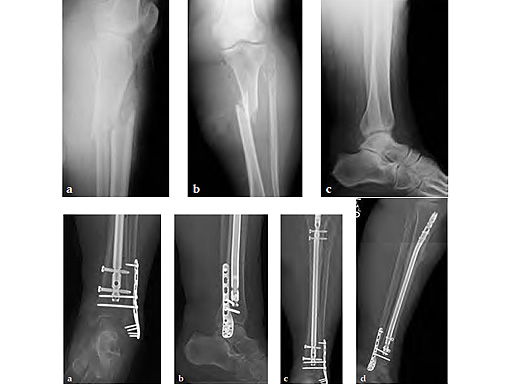

Case 2: 80-year-old morbidly obese female. Post motor vehicle collision with open proximal third tibial shaft fracture, closed lateral malleolar fracture and fibular neck fracture, and distal tibiofibular syndesmotic disruption with ankle capsular injury.